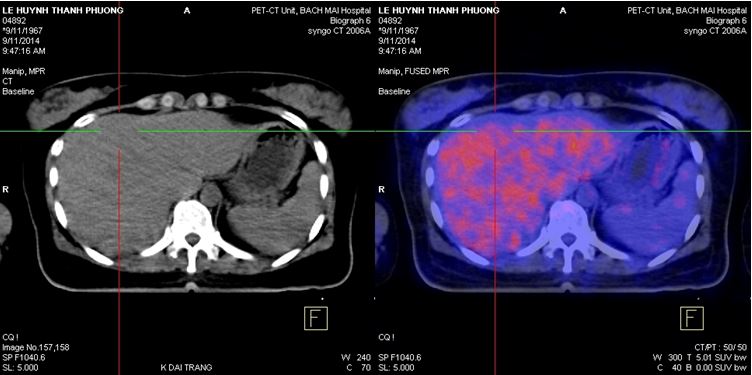

Bệnh nhân được chụp PET/CT đánh giá, (ngày 9/11/14) kết quả cho thấy: Gan: Hạ phân thùy VI có vùng tăng tỷ trọng trên hình ảnh cắt lớp vi tính nhưng không tăng hấp thu F-18 FDG, kích thước 1,8x 2,1cm. Ngoài ra không thấy bất thường khác.

Hình 4,5,6: Kết quả PET/CT sau điều trị (vòng tròn đỏ chỉ tổn thương): khối tổn thương di căn tại gan trái đã thu nhỏ kích thước hơn trước